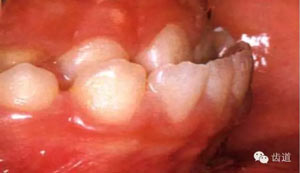

4.乳牙、恒牙萌出及替換:

如乳牙早失或滯留,恒牙早萌或早失。

5.齲齒、牙周病及口腔衛(wèi)生情況。

45.webp.jpg